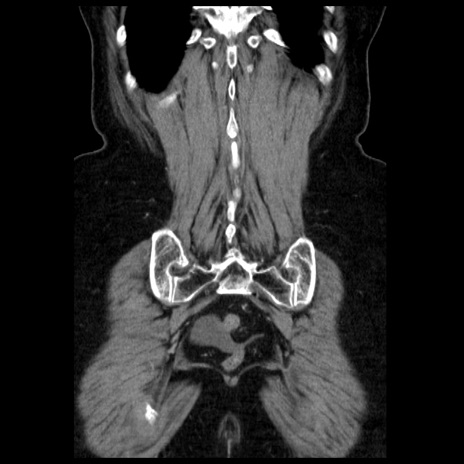

症例13(冠状断像)

【症例】70歳代女性

【主訴】腹痛、嘔吐

【現病歴】15時間程前(昨晩)より腹痛あり。今朝になっても症状の改善なく、嘔吐あり。腹痛も増悪あり、救急外来受診。

【既往歴】子宮癌全摘術後

【身体所見】意識清明、BP 121/72mmHg、P 74bpm、SpO2 100%(RA)、腹部:平坦・軟、腸雑音ほぼ聴取せず。下腹部・心窩部・臍左上に圧痛あり。反跳痛なし。

【データ】WBC 10600、CRP 0.15